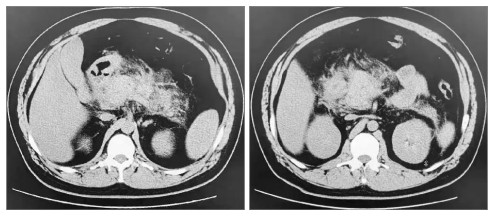

图 2图 3示:行血浆置换及CRRT治疗后,患者TG水平明显下降,腹痛也随之改善。患者于EICU共治疗4 d后一般情况显著改善,遂转入普通病区治疗。于入院第8日复查腹部CT可见胰周渗出较前吸收(见图 4),次日出院。出院后继续口服非诺贝特,3个月后随访查腹部CT可见患者胰腺体积、形态基本恢复,胰周渗出基本吸收,见图 5

左图为胰尾;右图为胰头 图 5 出院3个月后上腹部CT